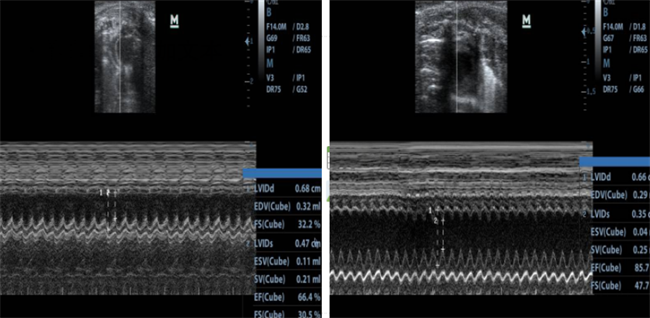

图2 心肌梗死模型大鼠心脏超声图像

针对上述问题,云克隆科研团队通过优化造模方法、制定标准化操作流程,成功构建了大鼠、小鼠、兔心肌梗死动物模型。该模型体系在梗死面积、心功能指标等关键维度上保持了高度一致性与可重复性,能精准模拟临床心梗的病理特征,为药物靶点验证与药效筛选提供了可靠的临床前研究载体,帮助科研人员将更多精力回归到核心机制研究本身。